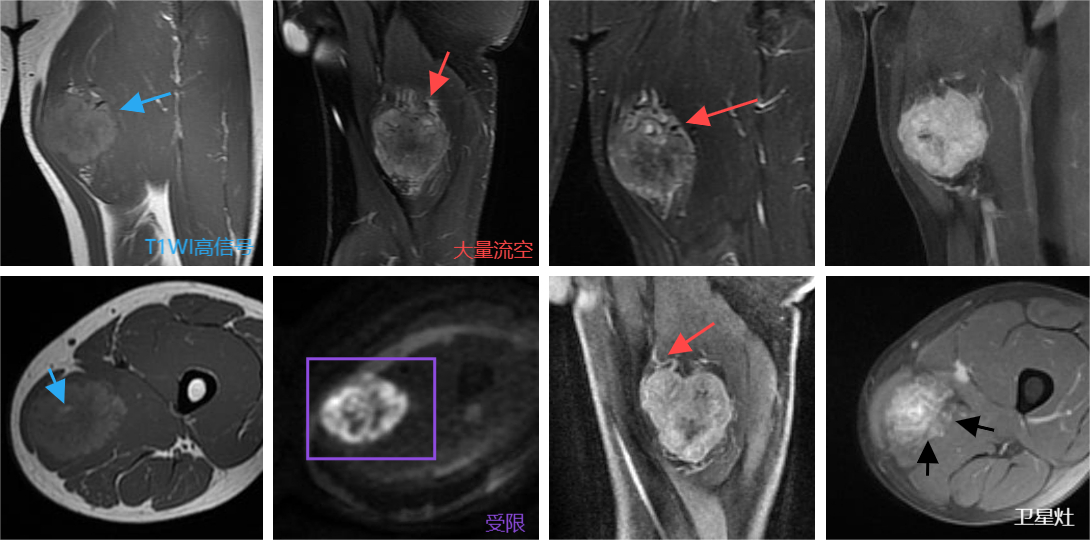

男,25岁。

左大腿内侧疼痛两个月,自觉能触摸到肿块。

病理结果:结合免疫组化,左大腿内侧肿物符合腺泡状软组织肉瘤。

影像表现:左大腿内侧肌间隙见团块状异常信号,边界尚清,形态尚规则,T1WI呈等稍高信号,内见点状更高信号,T2WI呈不均匀高信号,上缘多发流空血管影,弥散明显均匀受限,增强呈明显强化,见强化增粗的血管影,背侧另见多个小结节强化灶,边界欠清。

影像表现:主要依靠MR检查

1.ASPS的生长方式为膨胀式为主,对周围组织、器官浸润较少发生,但肿瘤也会沿肌肉间隙或筋膜与骨间隙生长,反映其侵袭性生物学特性。当肿瘤生长体积较大时,对周边血管和淋巴管压迫或侵犯,造成周围软组织水肿。同时,肿瘤内大量动-静脉瘘的存在,也会造成循环障碍从而引发水肿。

2. 肿瘤周边卫星灶: 恶性软组织肉瘤容易复发的主要原因为肿瘤周边存在卫星灶,这些卫星灶位于肌肉间隙或皮下的脂肪组织内,如术前不做影像学评估极易发生肿瘤残留。部分卫星灶早期并不能在影像学检查中被发现。

3.ASPS属于富血供肿瘤,肿瘤内存在大量蜿蜒迂曲的血管,同时具有部分动-静脉瘘。这些血管大部分在MRI图像上表现为流空信号。T1WI高信号的原因推测有三:其一,肿瘤血管丰富,容易形成动静脉短路,静脉淤血形成慢血流,血液瘀滞出现T1WI高信号;其二,静脉压力增大,通透性增大,富含蛋白的水分外溢导致;其三,肿瘤高度侵袭性破坏血管或血管自身通透性增大,导致出血。

4.T2加权图像上肿瘤为信号极不均匀,这是由于肿瘤组织内的出血、坏死、瘢痕形成等因素所造成出血为低信号,小片的坏死囊变为高信号,瘢痕组织则为等信号。增强后肿瘤强化显著,同时能够较长时间保持强化,除了与肿瘤内血管密集和走行蜿蜒迂曲密切有关外,还与肿瘤巢之间血管内皮细胞形成的毛细血管状结构使得肿瘤内“血池”容积较大有关。

总结:

年轻人深部软组织占位

周围及内部多发流空血管

T1WI高信号

卫星灶易复发